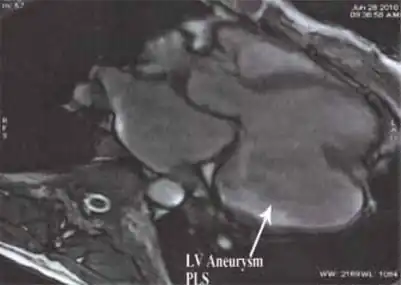

-

MRI showing the posterobasal left ventricular aneurysm -